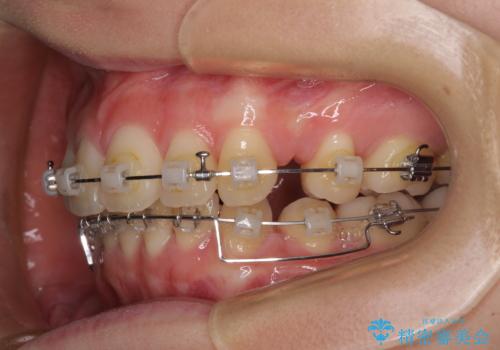

- クリアブラケット

前突間を改善するため、上顎左右の第一小臼歯を抜歯してワイヤー装置にて矯正治療を行うこととしました。

深い咬み合わせは上顎前歯を引っ込ませる大きな障害となるため、咬み合わせの改善が非常に重要となります。やや期間はかかりましたが、当初狙った通りの仕上がりで治療を終えることができました。